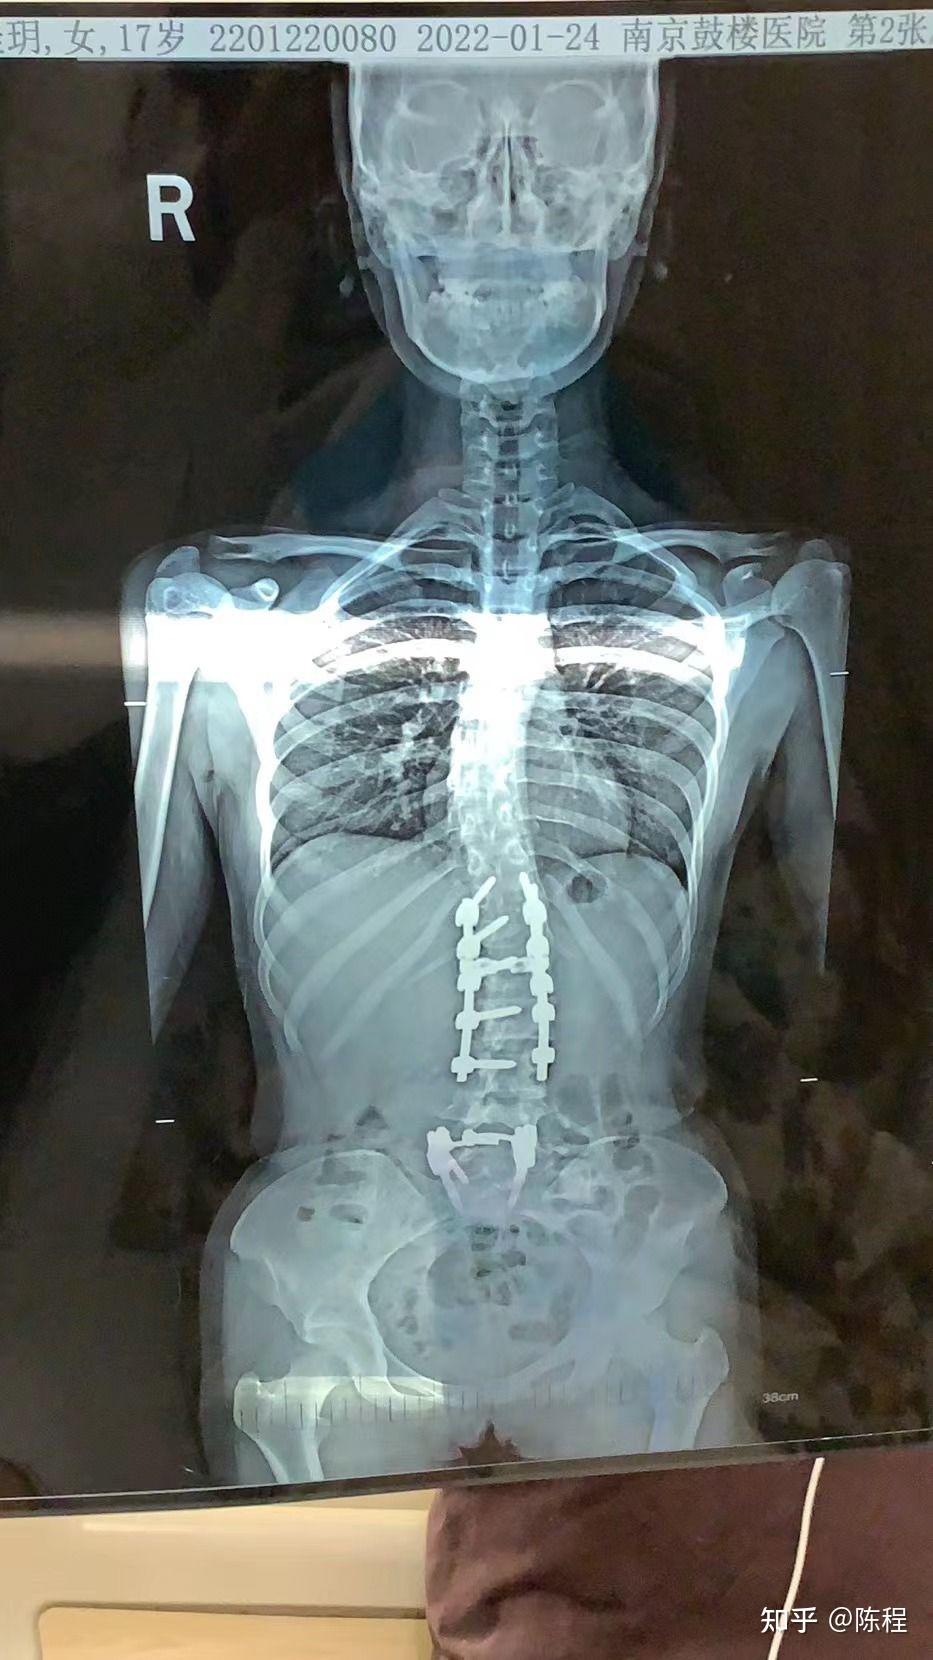

因为疫情一直在外地,特发性脊柱侧弯的小姑娘术后五个月才来复查

图片尺寸1440x1920